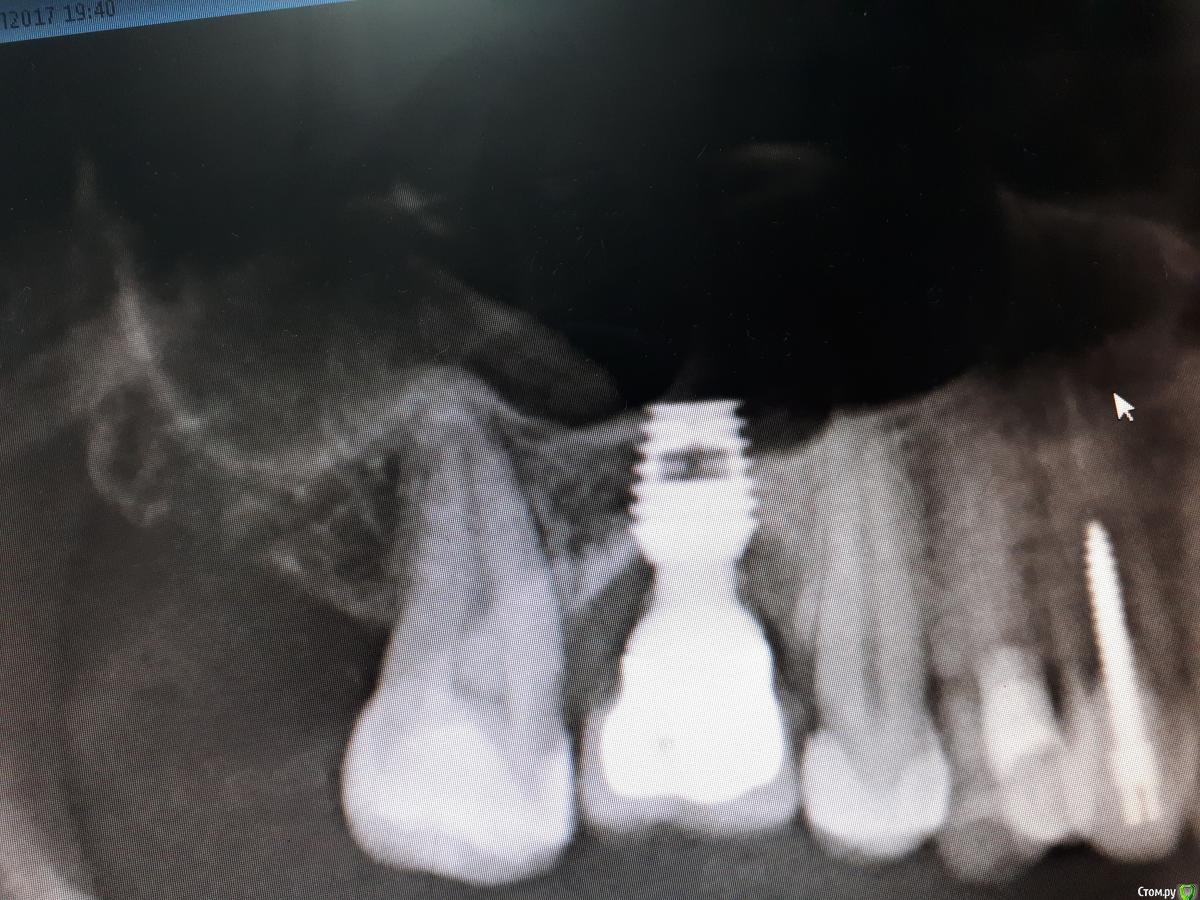

Rasim-AZ Опубликовано 24 июля, 2017 Поделиться Опубликовано 24 июля, 2017 Имплантолог в проекции 16 зуба, установлен около 3х лет назад, без костной аугментации, дефицит кератинизированной десны, грозное от деляемое, попадает пища с момента сдачи коронки (со слов пациентки). Что за система? И что делать? Ссылка на комментарий

AlexanderGudkov Опубликовано 24 июля, 2017 Поделиться Опубликовано 24 июля, 2017 Это БайконСнять коронку, поменять на форик, добавить десны, сделать новую коронку)) 1 Ссылка на комментарий

johniola Опубликовано 25 июля, 2017 Поделиться Опубликовано 25 июля, 2017 байкон шорт имплант Ссылка на комментарий